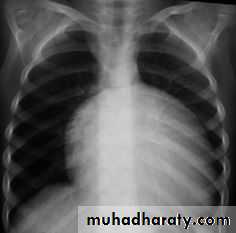

T.G.A represents about 5% of congenital heart defects, and it is the most common cyanotic lesion to present in the Newborn period . T.G.A is ventriculoarterial discordance secondary to abnormalities of septation of the truncus arteriosus, the aorta arises from the right ventricle, anterior and to the right of the pulmonary artery, which arises from the left

ventricle. This transposition results in desaturated blood returning to the right heart and being pumped back out to the body, while well-oxygenated blood returning from the lungs enters the left heart and is pumped back to the lungs. Without mixing of the two circulations, death occurs quickly. Mixing can occur at the atrial (patent foramen ovale/ASD), ventricular (VSD), or great vessel (PDA) level

CLINICAL MANIFESTATIONS

History of cyanosis from birth is always present.

Symptoms of congestive heart failure (CHF) with dyspnea and feeding difficulties may develop during the newborn period

On examination:-

Moderate to severe cyanosis and tachypnea.

No VSD no murmur, VSD holosystolic murmur, and there may be murmur of RVOT or LVOT obstruction.

There may be features of heart failure.